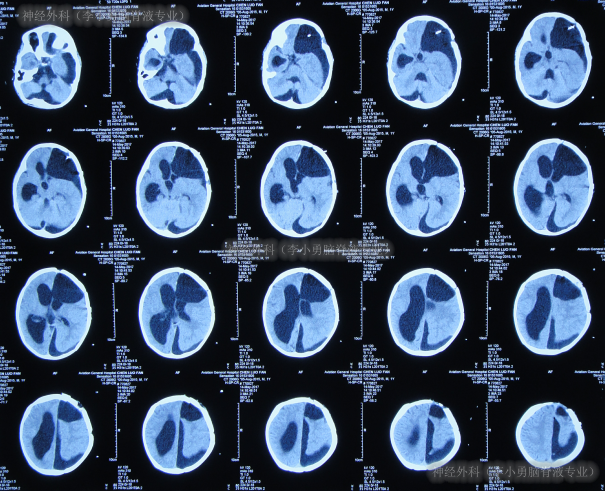

2017年10月8日(李小勇脑脊液专业治80天)出院,出院时:精神状态好,肢体活动正常,能自己走路稍不稳,可简单言语交流;头围由入院时55cm缩小至51.5cm(图-22);出院时头颅CT示脑室分流术后状态,无异常(图-23)。

图-22:2017年10月8日

图-23:2017年10月8日头颅CT

三、出院后随访

出院后2月即2017年12月,来院复查,复查时:走路较出院时变稳(图-24)。

图-24:2017年12月4日

出院后5个月即2018年3月4日,来院复查:3岁,走路正常,言语交流正常,智力发育基本正常(图-25)。

图-25:2018年3月4日〔本典型病例所涉及的图片和视频均经患者本人或家属同意,如有异议,请联系该内容发布方〕